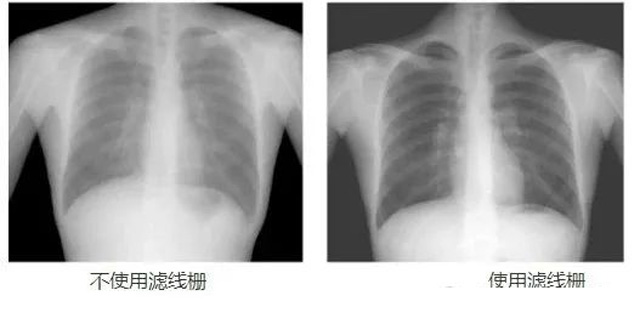

DR影像X射線在醫(yī)學檢查成像有著廣泛的使用。但是它的散射線影響成像質量問題。濾線柵的發(fā)明使用很好的解決了這個問題,構造簡單鉛條粗,密度和柵比規(guī)格單一,能減散射線但吸收較多原發(fā)射線。伴隨這醫(yī)療影像設備技術的發(fā)展,這個濾線柵的工藝制造技術有改進,鉛條變薄,柵密度和柵比有更多的選擇。特別是材料方面有新組合,填充物也依不同成像要求優(yōu)化。特別是移動DR這類型的DR設備的出現(xiàn),濾線柵也設計成立方便拆卸形的,方便使用。被照體情況決定是否使用,更好平衡成像質量與射線劑量。